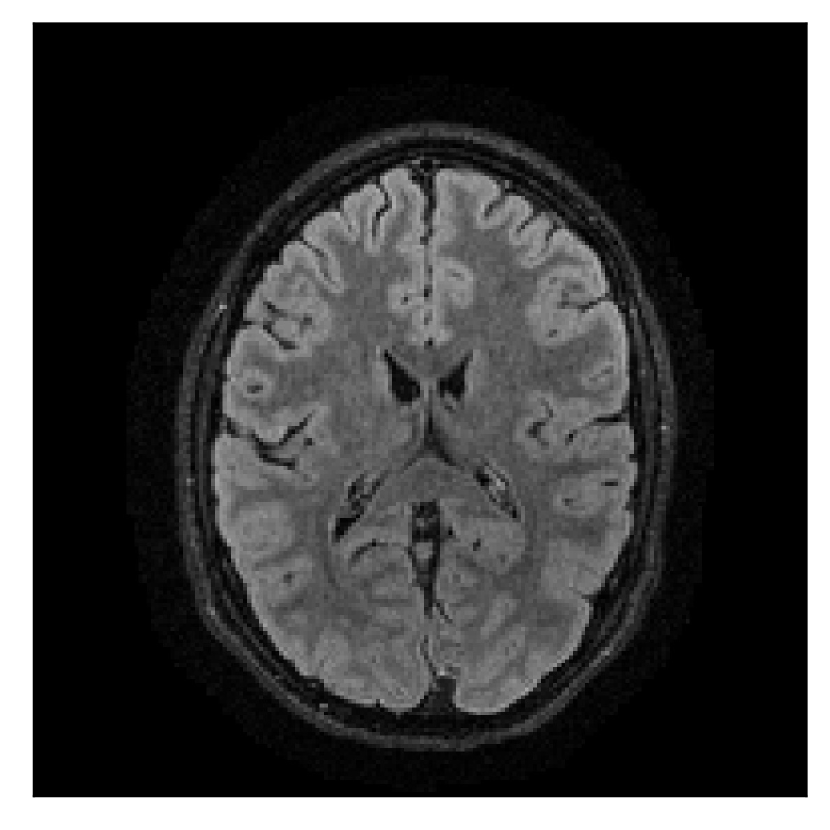

4.1 Experiment 1: robustness test

We gather the results for the robustness test described in Section 3.1 (volunteer 1) in Figures 2, 4, and 6 for motion corruption mechanisms associated to one, two, and five changes of position, respectively. Furthermore, we juxtapose the corrected images with varying degrees of corruption in Figure 8. We observe that the proposed method consistently ameliorates the corrupted scan. The quality indexes based on PSNR and SSIM show only a modest decrease in correction quality as a function of motion complexity (Figure 8).

| Section 3.1, Figure 2 | Sagittal | 23.94 | 27.95 | 0.7068 | 0.7936 |

| Coronal | 26.66 | 29.82 | 0.7653 | 0.8332 | |

| Axial | 25.40 | 30.16 | 0.7616 | 0.8490 | |

| Section 3.1, Figure 2 | T2-FLAIR | Completely corrected | Some blurring | No additional artifacts | Good grey white matter differentiation |